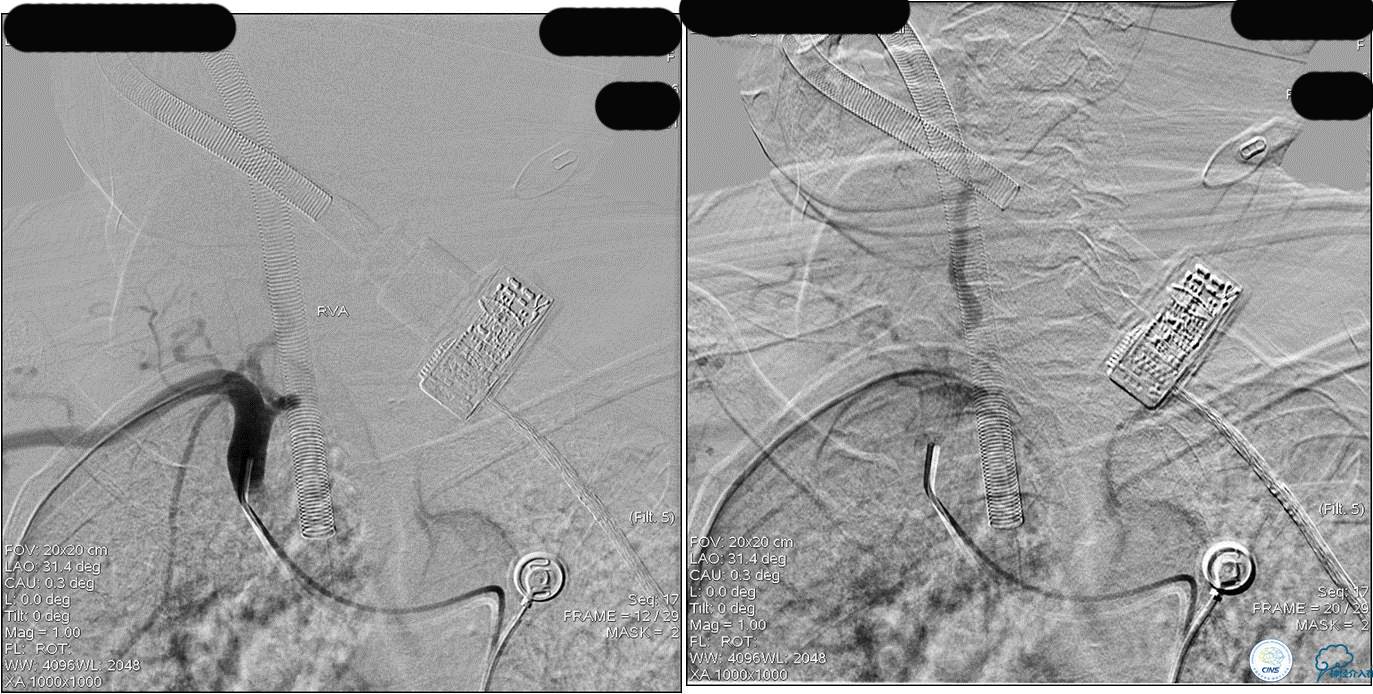

》DSA资料(前2次取栓,未取出,soli 4-20)

》DSA资料(第3次取栓)

第3次取出血栓

★后循环取栓病人,若股动脉入路较差,可以考虑经桡动脉进行。

★基底动脉尖端的血栓偏向哪侧,应该将Solitaire支架放入同侧的大脑后动脉,这样取栓的成功率较高一些。